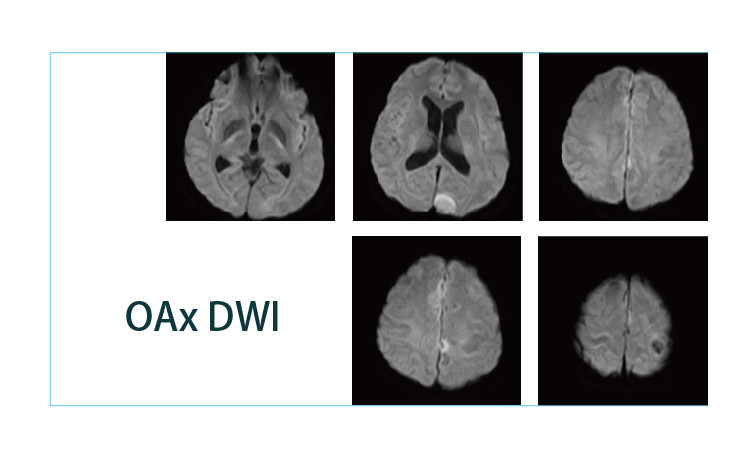

【朗润影像档案】磁共振影像病例分享(编号20190426)

【朗润影像档案】磁共振影像病例分享(编号20190419)

【朗润影像档案】磁共振影像病例分享(编号20190412)

【朗润影像档案】磁共振影像病例分享(编号20190405)